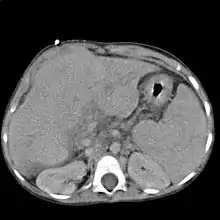

| شکم فردی سیروزی با نشانگان آسیت و بمانند سر عروس دریایی(انشعابات متعدد) | |